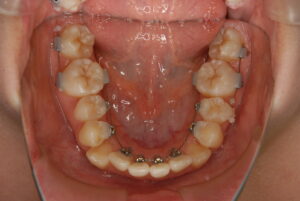

実際の症例紹介(20代女性/裏側ワイヤー矯正)

治療前

治療後

・主訴:八重歯と前歯の突出

・治療法:裏側からのワイヤー矯正(リンガル)

・治療期間:約1年半〜2年(目安)

・予想される副作用・リスク:装置装着後の違和感・疼痛、発音のしづらさ、一時的な咀嚼効率低下、ブラッシング不良によるむし歯・歯周病リスク など

※写真は代表的な症例です。口腔内の状態により治療法や期間は異なります。詳細は初診相談でご説明します。